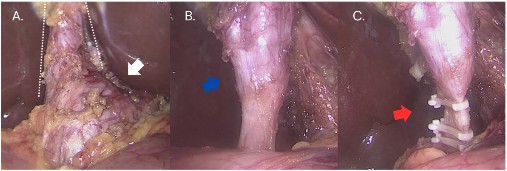

Ante el diagnóstico de quiste de colédoco y pólipos vesiculares, se indicó la intervención quirúrgica. La paciente fue sometida a una colecistectomía laparoscópica con resección del colédoco y derivación biliodigestiva en Y de Roux. Durante el procedimiento quirúrgico, se encontró una vesícula biliar de 8 x 5 cm con paredes delgadas, y el conducto cístico tenía aproximadamente 5 a 6 cm de largo y 3 cm de diámetro. Asimismo, a nivel del colédoco, se evidenció una dilatación fusiforme que se extendía desde la desembocadura de la vesícula biliar hasta el conducto retroduodenal (Figura 4).

Figura 4 A. Imagen intraoperatoria donde se aprecia el conducto cístico (líneas punteadas) desembocando en el quiste de colédoco (flecha blanca), tipo Ia según la clasificación de Todani. B. Imagen intraoperatoria donde se observa el término de la dilatación quística (flecha azul) en la porción distal de la vía biliar. C. Imagen intraoperatoria donde se observa la sección distal del quiste de colédoco (flecha roja).